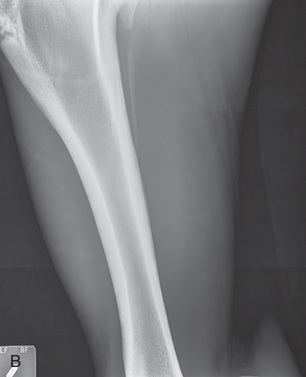

| Metacarpal/metatarsal cannon bone (M3) | Dorsoproximal-palmarodistal (DPr-PaDi) | Dorsopalmar (DP) |

| Lateromedial (LM) | Lateral (L) | |